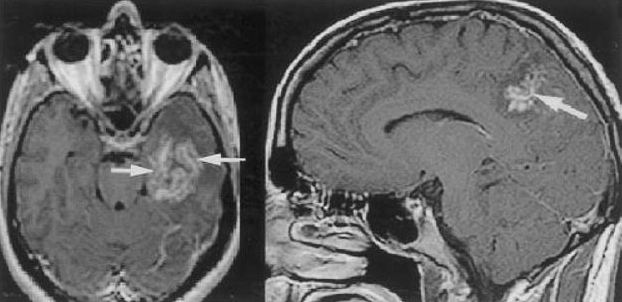

Dwóch różnych pacjentów z mózgowym zakażeniem przywrami

Paragonimus spp. to jedyna ssakowa przywra płucna, która może zarażać ludzi. Szacuje się, że na świecie zarażonych jest 20 milionów ludzi, z czego 10 milionów w samych Chinach. Zakażenie u ludzi jest najczęściej spowodowane spożyciem słodkowodnego kraba lub raka. W pełni ugotowane kraby i raki nie przenoszą zakażenia, ale wiele regionalnych potraw wykorzystuje kiszenie lub marynowanie zamiast gotowania, a to potencjalnie może już być źródłem zakażenia. Udomowione koty, psy, dziki i świnie również mogą być nosicielami. W ciągu 2 do 8 tygodni larwy migrują przez ścianę jelita i otrzewną, aby zaatakować miąższ płuc. Larwy pozostają w płucach do momentu osiągnięcia dojrzałości, po czym migracja powraca. W każdej fazie choroby często występują migrujące masy podskórne, które zawierają niedojrzałe robaki i najczęściej lokalizują się w dolnej części brzucha. W ciągu 4 do 6 miesięcy od zakażenia rozwijają się objawy płucne, od łagodnego kaszlu do piorunującej duszności lub krwioplucia.